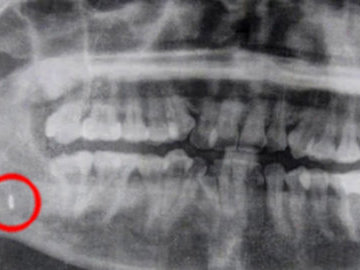

- Московские врачи: какие предметы проглатывают дети до пяти лет